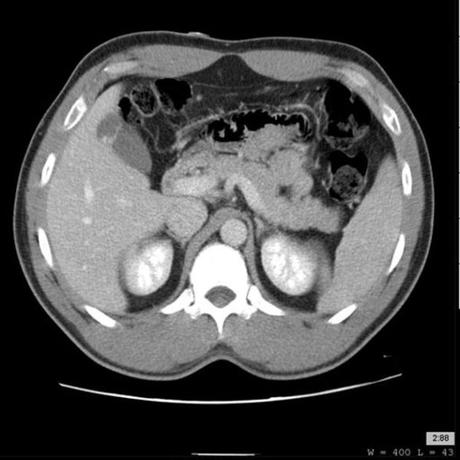

Las tapas frigias son la variante anatómica congénita más común de la vesícula biliar . Denota el plegamiento del fondo nuevamente sobre el cuerpo de la vesícula biliar y es asintomático sin importancia patológica.

CT / MRI multifase

Por lo general, diferencia claramente las tapas frigias de las lesiones masivas.

La vesícula biliar se presenta con un plegamiento de su fondo.